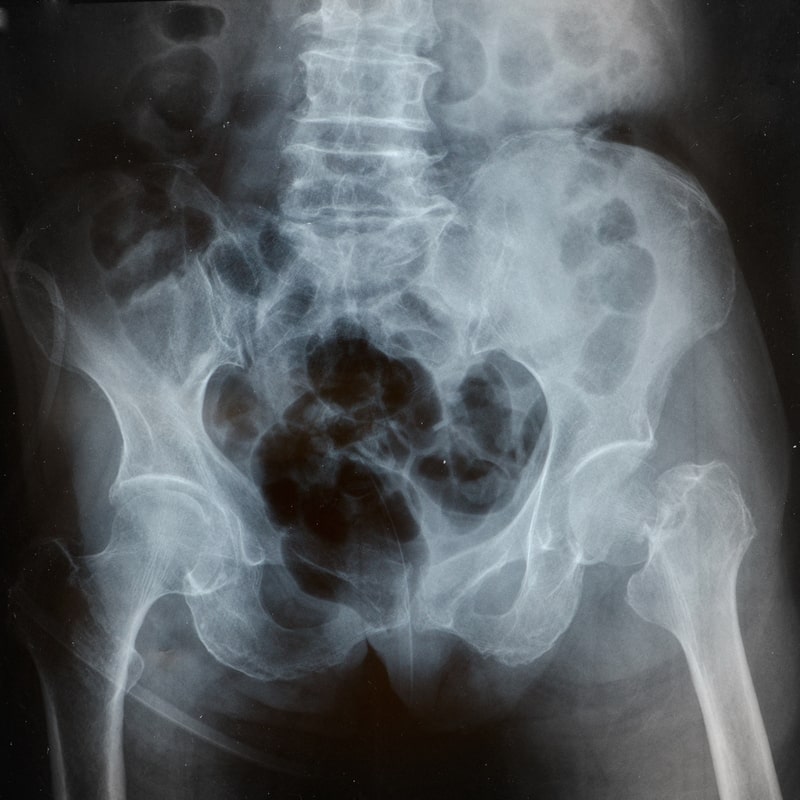

Quais os locais mais atingidos pela osteoporose?

No Brasil, por ano, de acordo com a Sociedade Brasileira de Endocrinologia e Metabologia (SBEM), ocorrem cerca de 2,4 milhões de fraturas decorrentes da osteoporose.

Os locais mais comuns atingidos pela osteoporose são a coluna (vértebras), a bacia (fêmur), o punho (rádio) e braço (úmero).